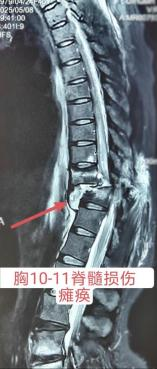

患者,女,2025年5月,不慎从4米高处坠落,伤后立即下肢瘫痪且失去知觉,伴近事遗忘,就近送往当地医院,检查提示胸11骨折伴脊髓损伤,头部CT提示脑挫伤,入院后给与对症治疗,脑挫伤改善后于伤后第七天行胸椎骨折复位内固定+椎管减压手术,术后持续下肢瘫痪,感觉及运动消失,大小便无知觉。

入院检查:神志清楚,肚脐以下感觉消失,下肢肌力0级,肌张力消失,下肢病理反射、生理反射均未引出,可引出肛门收缩,留置导尿。诊断:胸10-11脊髓损伤(ASIA B级),截瘫,神经源性膀胱,神经源性肠道。

图片图片

复位前MRI

复位后MRI